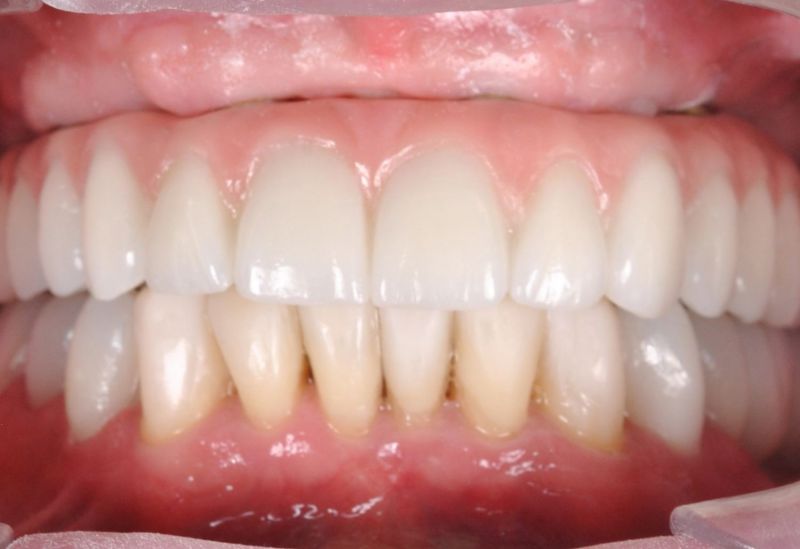

Wykonana praca protetyczna:

- most pełnołukowy na sześciu implantach

- korony na zęby własne w łuku dolnym

- korony na implantach w miejscach braków zębów

- odbudowa flow-injection zębów dolnych przednich